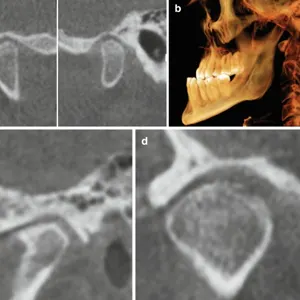

CBCT 3D Imaging

Cone Beam CT scans provide detailed three-dimensional views of the TMJ anatomy, detecting structural changes, bone remodelling, and joint space evaluation.